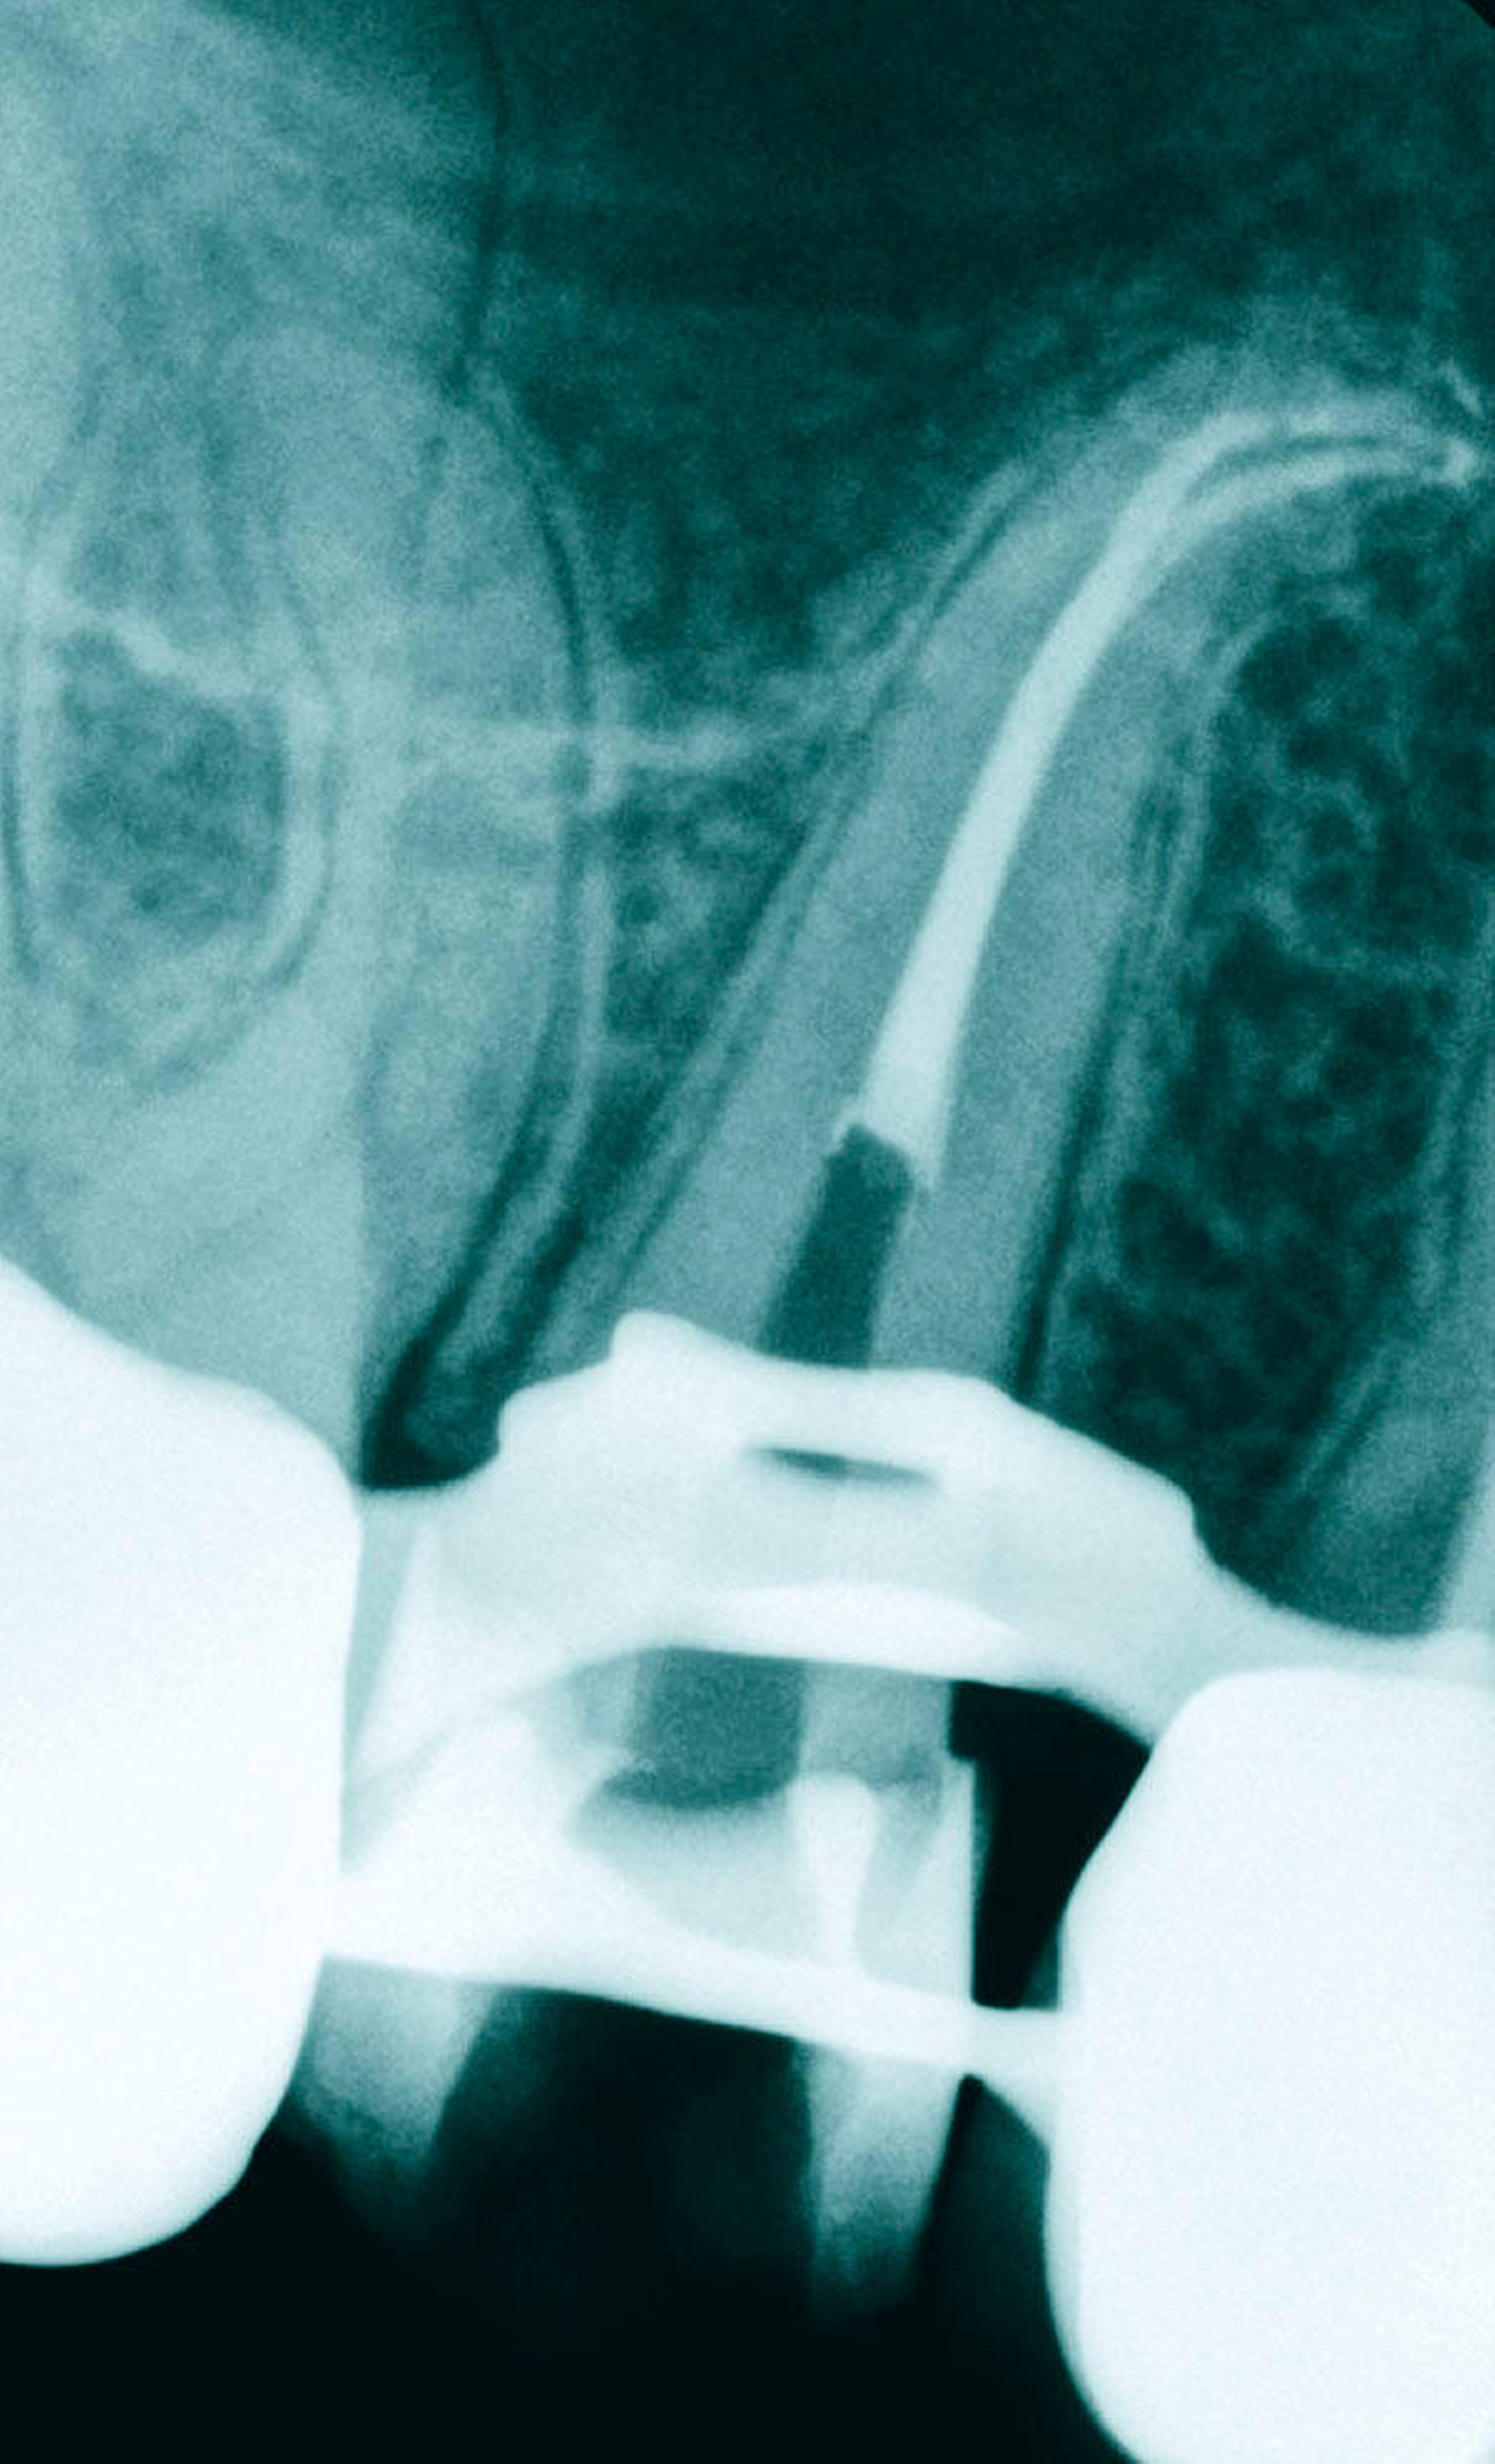

Die Krümmungen folgen bei beiden Zähnen in der Regel dem distalen Krümmungsmerkmal. Eine starke Ausdehnung der Kieferhöhle scheint jedoch für starke apikale Krümmungen der Wurzeln nach mesial oder distal verantwortlich zu sein. Ebenfalls nicht selten anzutreffen sind Doppelkrümmungen der Wurzeln (Abbildung 3).